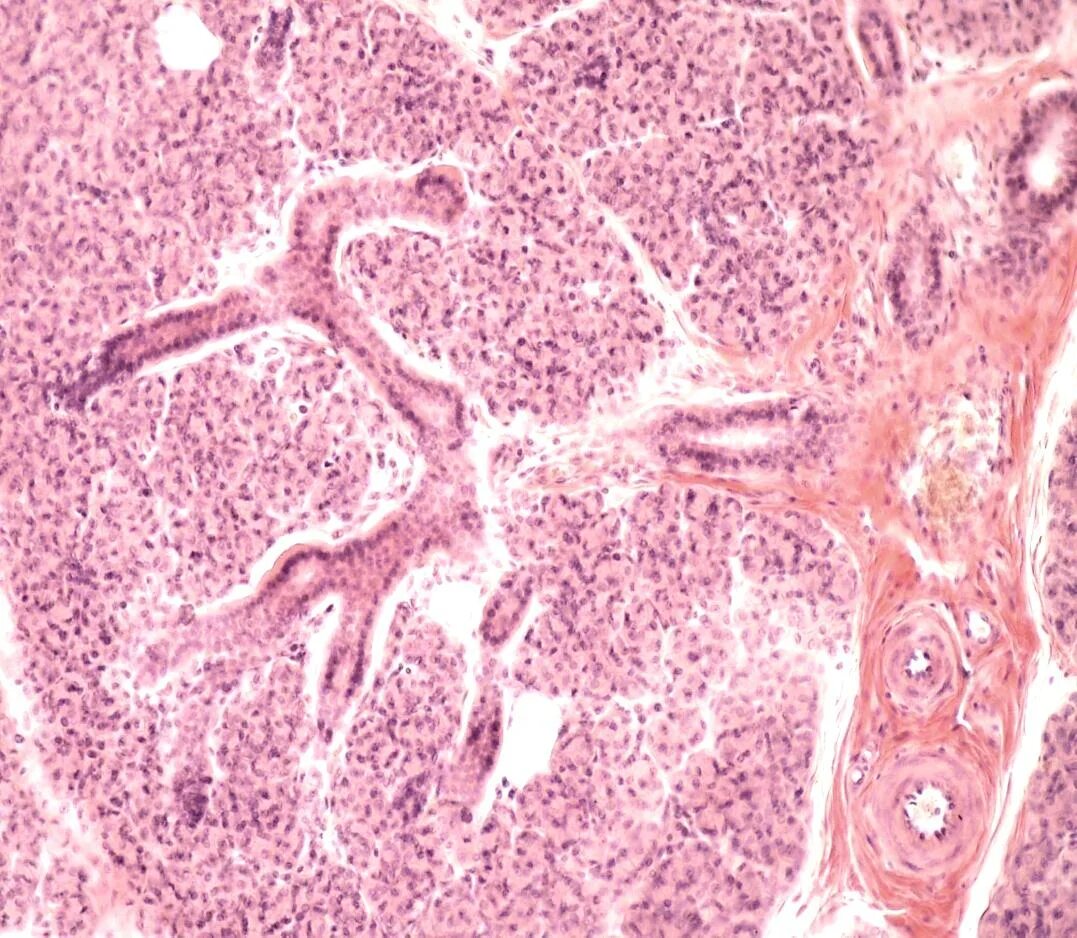

Околоушная гистология